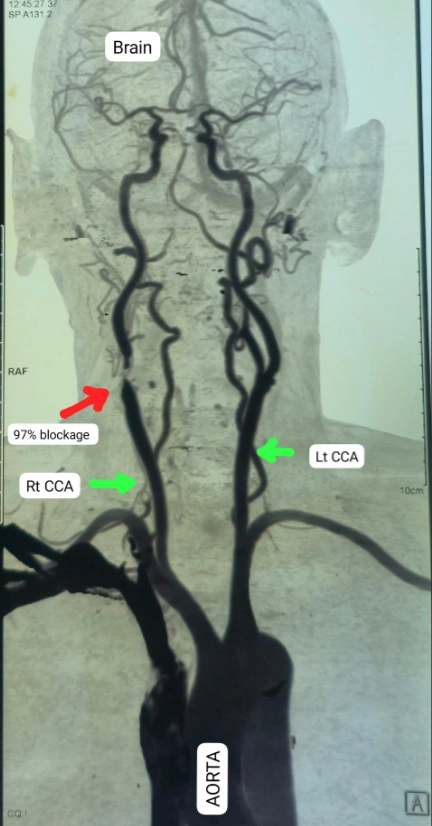

मरीज को थी लकवे और दृष्टिदोष की शिकायत- बालाघाट निवासी 70 वर्षीय मरीज को पिछले दो वर्षों से बार-बार लकवा, चक्कर, एक आंख से धुंधला दिखना और सुनाई न देने जैसी समस्याएं हो रही थीं। प्रारंभिक जांच के बाद कैरोटिड सीटी एंजियोग्राफी कराई गई, जिसमें पता चला कि मरीज की दाहिनी कैरोटिड आर्टरी में 95% से अधिक रुकावट थी। इससे मस्तिष्क को रक्त की आपूर्ति बाधित हो रही थी।

सर्जरी थी बेहद जोखिमभरी-डॉ. के.के. साहू ने परिजनों को स्पष्ट किया कि इस सर्जरी में जान का खतरा हो सकता है, क्योंकि ऑपरेशन के दौरान यदि कोई भी प्लाक का टुकड़ा या हवा का बुलबुला मस्तिष्क में चला जाता तो मरीज ब्रेन डेड हो सकता था। इसके बावजूद मरीज एवं परिजनों ने ऑपरेशन की सहमति दी।सर्जरी के दौरान कैरोटिड शंट नामक विशेष उपकरण का प्रयोग किया गया ताकि मस्तिष्क में रक्त प्रवाह लगातार बना रहे। ब्लॉकेज हटाने के बाद नस को बोवाइन पेरीकार्डियम पैच से मरम्मत कर पुनः सामान्य किया गया। सर्जरी पूरी तरह सफल रही और मरीज अब स्वस्थ होकर डिस्चार्ज होने की स्थिति में है।डॉ. साहू के मुताबिक, गले की नस के ब्लॉकेज खोलने की अन्य विधि कैरोटिड आर्टरी स्टेंटिंग है पर सर्जरी जिसको कैरोटिड एंडआर्टरेक्टॉमी कहा जाता है, वह सुरक्षित होता है।